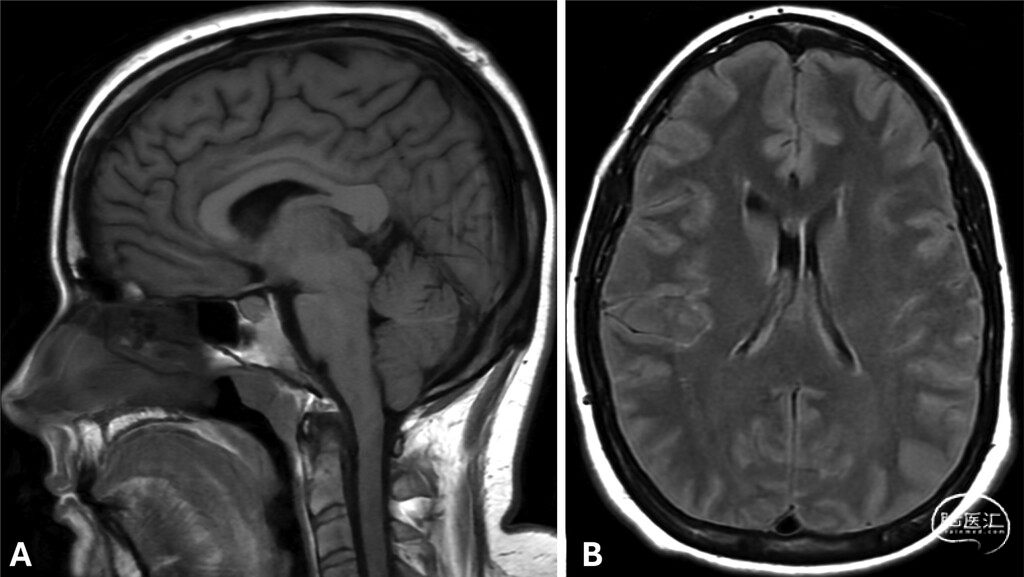

● 首次头颅非增强MRI显示符合颅内低压的影像学表现(图1)。因患者当时妊娠34周,暂缓CTM检查,由麻醉科医师在无影像引导下为其实施了非靶向腰椎硬膜外血贴治疗,术后症状完全缓解。6个月后,患者因症状复发再次就诊。复查增强头颅MRI仍提示颅内低压表现,并新增硬脑膜弥漫性强化(图2)。全脊柱MRI显示腹侧硬膜外脑脊液信号积聚,高度提示1型脑脊液漏(图3)。CTM证实存在T4至T11节段腹侧硬膜外造影剂积聚,但未能明确漏口位置。

图1:头颅非增强MRI初始图像,显示颅内低压典型表现。A:T1加权像,垂体增大、鞍上池与桥前池变窄/消失、乳头体-脑桥距离缩短、小脑扁桃体下移。B:T2加权FLAIR像,双侧薄层硬膜下积液。